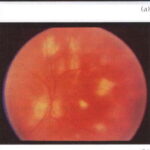

OCULAR DISEASE

Although patients with vitiligo do not usually have ophthalmologic complaints, they can have several ocular findings. Pigmentary abnormalities of the iris and retina may occur. Choroidal abnormalities have been reported in up to 30 percent of patients and iritis in approximately 5 percent. Uveitis can be a frequent ocular manifestation. Exophthalmos may occur in the setting of concomitant Graves disease. Visual acuity is generally not affected.

VOGT-KOYANAGI-HARADA SYNDROME

The Vogt-Koyanagi-Harada syndrome (VKH) consists of vitiligo in association with uveitis, aseptic meningitis, dysacusis, tinnitus, poliosis, and alopecia. It is a rare, systemic, T-cell-mediated autoimmune disorder. VKH syndrome is associated with other autoimmune disorders such as autoimmune polyglandular syndrome, hypothyroidism, Hashimoto thyroiditis, and diabetes mellitus. VKH syndrome classically occurs in three phases. During the first phase, the meningoencephalic phase, patients may have headache, meningismus, seizures, muscle weakness, or paralysis after a prodrome of fever, malaise, nausea and vomiting. Subsequently, the acute ophthalmic phase occurs when patients may develop photophobia, eye pain, and altered visual acuity. Patients may develop uveitis, iridocyclitis, choroiditis, and retinal detachment during this phase and can later develop complications such as cataracts and glaucoma. Vitiligo, alopecia, and poliosis22 usually follow, but can occur before the other manifestations.

ALEZZANDRINI SYNDROME

The constellation of clinical findings in Alezzandrini syndrome includes facial vitiligo, poliosis, deafness, and unilateral tapetoretinal degeneration. The etiology remains poorly understood, but as in vitiligo and VKH syndrome, autoimmune processes are thought to be involved. Only a few cases have been reported since the first description of a patient with vitiligo, poliosis, and unilateral retinitis in 1959.23